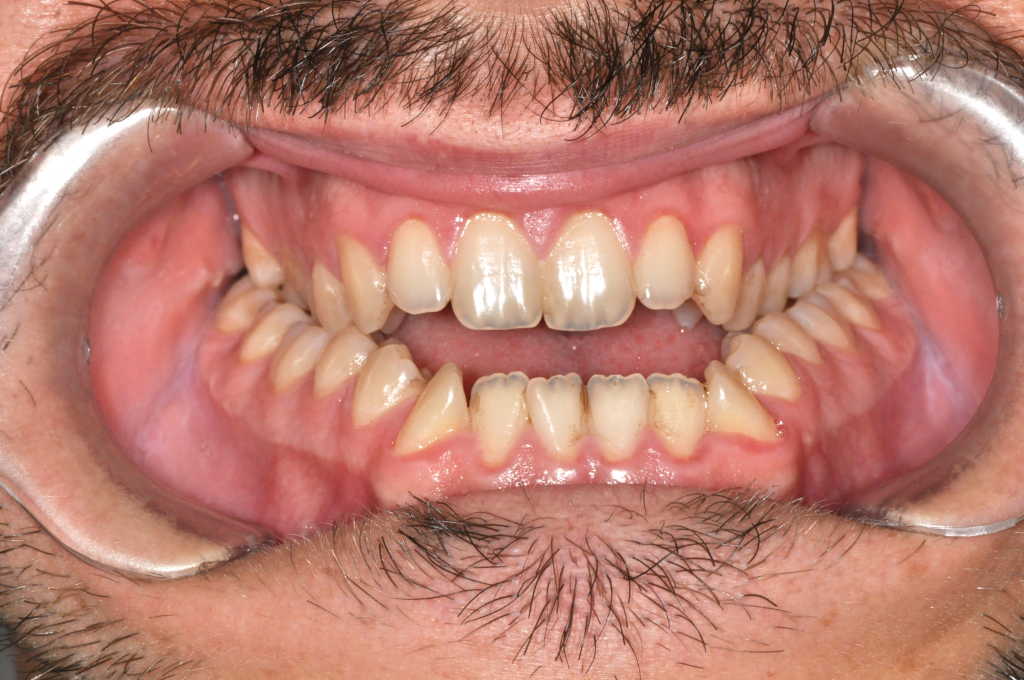

Előtte fogsor - Bulldogharapás + nyitott harapás kombinált kezelése

Utána fogsor - Bulldogharapás + nyitott harapás kombinált kezelése

Ebben az esetben két harapási rendellenesség volt jelen egyszerre.

Az alsó állkapocs előrehelyezett volt (bulldogharapás),

miközben elöl nyitott harapás alakult ki.

Ez állcsonti probléma volt, amely fogszabályozással önmagában nem kezelhető.

A kezelést fogszabályozással készítettük elő, majd az alsó állkapcsot kontrolláltan

hátramozgattuk,

a felső állkapcsot pedig előre és lefelé pozícionáltuk.

Eredmény: záró harapás, működő rágás, harmonikus arcprofil.